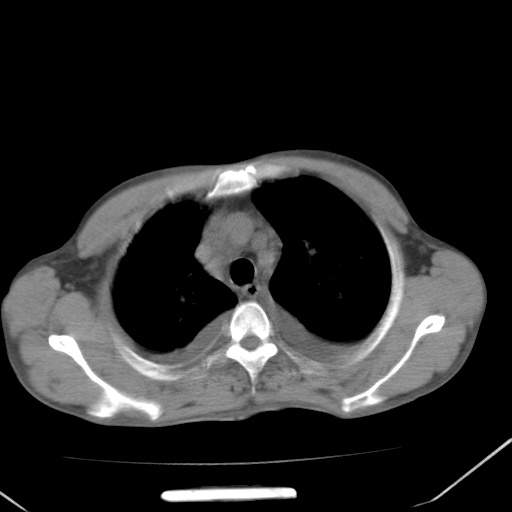

男、42岁、咯血3天。既往有甲亢、贫血、血尿蛋白尿史多年。血象:wbc:6.   中性粒:70.6%。

双肺野对称性磨玻璃影,分布于内中带,双侧胸水,患者有咯血。

双肺野广泛对称性磨玻璃影、实变影,以肺门为中心,主要分布于内中带,符合典型肺泡性肺水肿;伴双侧胸腔少量游离积液。结合患者既往病史且咯血就诊,支持多因素(尿毒症等)所致之肺水肿、肺出血、胸水;影像表现暂不考虑心源性水肿,且症状也不太符。需密切随诊结合临床治疗等进一步明确。

心影增大密度略低,双肺磨玻璃样高密度影及双侧胸腔积液,考虑心功能不全继发双肺肺水肿及双侧胸腔积液。心影密度略低,考虑贫血所致。